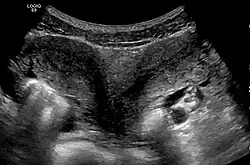

Utérus didelphe

Un utérus didelphe est une malformation de l'utérus survenant à la suite d'un défaut de fusion des canaux de Müller lors de la 7e semaine du développement du fœtus[1].